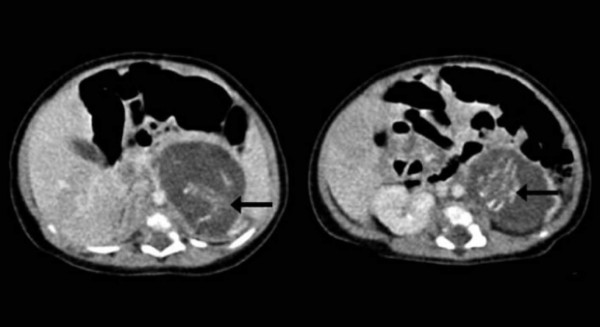

Un equipo de doctores describió el caso de una bebé recien nacida 'embarazada de gemelos' como un hecho médico extremadamente raro, tras encontrar lo que parece ser un par de fetos dentro del cuerpo de la bebé.

Los festos estaban unidos por cordones umbilicales en una clase de masa de placenta. Cada uno tenía cuatro miembros, piel, costillas, intestinos y tejido cerebral primitivo, de acuerdo con la publicación.

La razón de este extraño suceso, según afirman los especialistas, se debió a una fecundación errónea en el vientre de la madre, la cual habría producido que los fetos (sus dos hermanos) se gestaran en su interior. El caso, con todo, es conocido. Se llama 'fetus in fetu' y sólo se produce una vez en cada 500,000 nacimientos.

Las dos formas encontradas tenían diferentes pesos pero igual desarrollo de órganos, coincidente con un feto de 10 semanas de gestación. Tenían espinas dorsales y “genitales externos ambiguos”, aunque no contaban con cráneos.